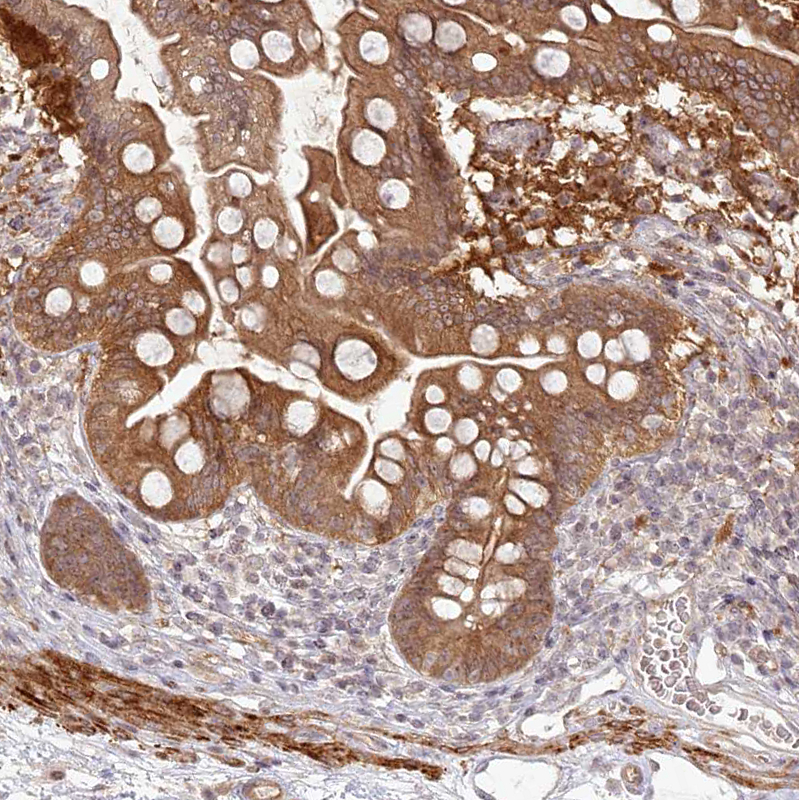

Immunohistochemical staining of human small intestine shows strong cytoplasmic positivity in glandular cells.